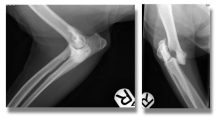

Treatment of a radius and ulna fracture in a Whippet

By Eastcott Referrals Orthopaedic Surgeon Fabio Frazzica A 1-year-old female Whippet presented with a distal diaphyseal, simple, transverse, closed ...